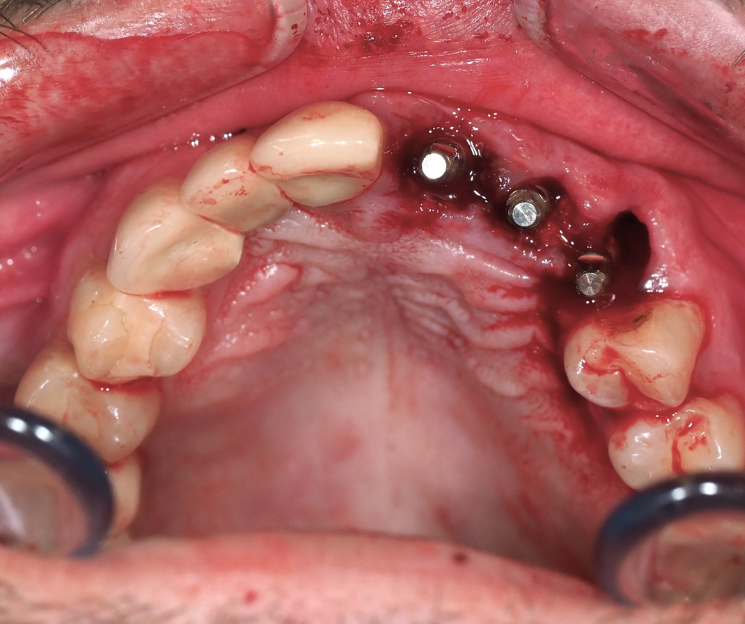

Extracción de piezas 21, 22 y 23 con infección activa

Paciente con infecciones de origen dental que comprometían severamente el hueso alveolar en la zona anterior superior. Se realizó la extracción de los dientes 21, 22 y 23, y se optó por una rehabilitación inmediata mediante implantes córticobasales.

Esta combinación permitió anclar los implantes en hueso cortical, que mantiene su estabilidad incluso en presencia de procesos infecciosos en el hueso alveolar. El resultado: rehabilitación funcional y estética el mismo día de la cirugía.

La rehabilitación postextracción de los dientes 21, 22 y 23 con implantes córticobasales no es un caso aislado. Es un ejemplo claro de cómo la odontología moderna puede resolver situaciones complejas de forma inmediata, estética y funcional.